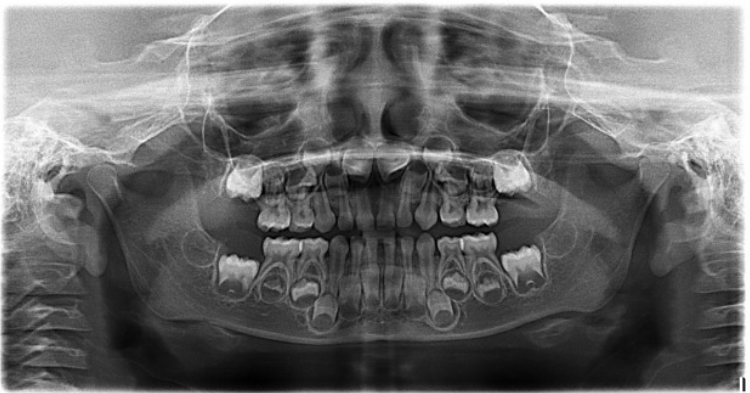

The following radiograph is an image which shows the upper and lower jaws of a child with a dental age of about four and half years.

All their primary teeth are present in their mouth, and the permanent teeth are in varying stages of development. Even though the crowns of the permanent molars have fully developed the teeth are not ready to emerge into the mouth. This will occur when approximately two thirds of the root structures have developed.

Description: Radiograph of a 4-year-old child with normal oral anatomy, showing a complete set of primary teeth, prior to the eruption of permanent teeth. Source: Radiopaedia.org